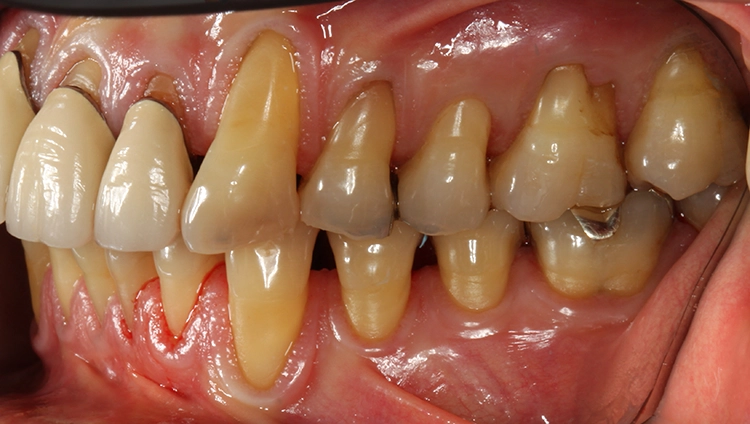

Egger/Wermuth/GrevenRote Ästhetik: Im Ober- und Unterkiefer zeigten sich generalisiert ausgedehnte Rezessionen mit bis zu 8 mm Attachmentverlust vor allem im Bereich der Eckzähne (Miller-Klasse III; Rezessionstyp [RT] 2 [69]. Das Band an keratinisierter Schleimhaut ist durchgehend vorhanden. Die Breite variiert im Eckzahnbereich von 1 mm bis zu 2 mm im Bereich der Unterkieferfrontzähne, der Prämolaren und Molaren (Abb. 1). Die fazialen Rezessionen sind mit approximalem röntgenologischem Attachmentverlust im koronalen Wurzeldrittel (Abb. 2) und Papillenverlust im Bereich zwischen den Kontaktpunkten und der approximalen Schmelz-Zement-Grenze assoziiert (Abb. 1). Der Patient verfügt über eine schmal geformte Oberlippe. Die Lachlinie verläuft mittelhoch (Abb. 3).

Parodontale Gesundheit bei Attachmentverlust, Bruxismus, Erosion. Abbildung 1 sowie 6 bis 9 zeigen den Anfangsbefund als intraoralen Fotostatus.*

Egger/Wermuth/GrevenAbb. 8 und 9: Rechts-links-Okklusion.